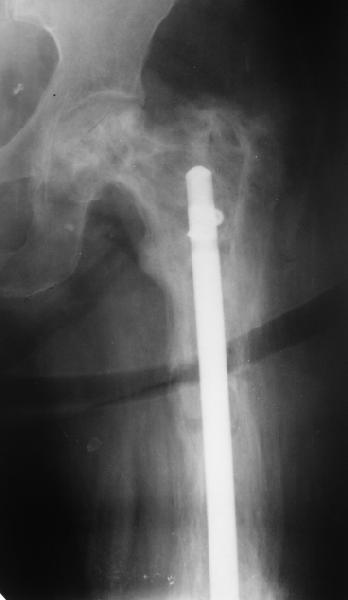

Еще один пример. Пациентка с юга России, прислала рентгенограммы через год. На сегодня прошло 2 г. 8 мес. после операции. Несмотря на не очень убедительный процесс сращения, пациентка ходит. Учитывая остеопороз при Педжете, решили, что динамизировать вообще не нужно.

При переломах на фоне болезни Педжета металлоконструкция часто служит эндопротезом, несущим нагрузку. Динамизация индивидуальна,- по рентген-динамике. Основной упор- на медикаментозную терапию- см. канд. дисс. Колондаева А.Ф.

Стержень можно было бы поставить подлиннее.

Анатолий Леонидович Баранецкий совершенно прав. Сращения ждать надо очень долго (несколько лет). Главное - гвоздь попрочнее и потолще. Раньше использовали мощный 4-гранный штифт ЦИТО. Можно и гвоздь с блокированием (блокировать только с одной стороны) - но ни в коем случае не полый. И ходить с тростью. Сейчас в России зарегистрирован очень хороший препарат (с декабря 2006 г.) - Акласта, по 100 мл - обычно хватает 1 (реже двух) инфузии для полной ремиссии (в Белоруссии он появился даже раньше, чем на Украине и в Россиии). Немного хуже Аредия, ее надо в сумме 180-240 мг, полная эффективность 84%. Все в\в кап. бисфосфонаты вызывают выраженную гипокальциемию. Поэтому приходится назначать по нескольку лет альфакальцидол под контролем Са крови (каждые 3-6 мес). Сперва по 6-8 капсул (капель), т.е 1,5-2,0 мкг, затем через 2-4 месяца - по 0,5-0,75 мкг. Препараты Са по 1-2 гр. в день, очень долго.